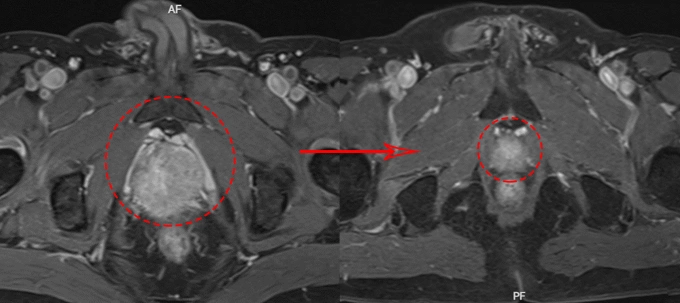

Chụp MRI tuyến tiền liệt của bệnh nhân trước (bên trái) và sau điều trị (bên phải). Ảnh: Bệnh viện Đa khoa Tâm Anh

Bác sĩ chỉ định sử dụng thuốc nội tiết tân bổ trợ gồm thuốc tiêm mỗi tháng một mũi và thuốc uống hàng ngày cho ông Chuyên. Sau một tháng, xét nghiệm máu cho thấy chỉ số PSA giảm về mức bình thường. 4 tháng sau, chụp MRI ghi nhận tuyến tiền liệt giảm kích thước đáng kể, từ 38 g còn 12 g, bệnh nhân hết khó tiểu. Tiếp đến, người bệnh được xạ trị gia tốc điều biến liều (IMRT) trong 37 buổi. Liều xạ được phân bổ theo kế hoạch, tập trung vào tuyến tiền liệt để tiêu diệt tế bào ung thư, giảm dần liều ra vùng ngoại vi để bảo vệ bàng quang, trực tràng và xương chậu, hạn chế tối đa tác dụng phụ.

Theo bác sĩ Sơn, tế bào ung thư tuyến tiền liệt dùng hormone sinh dục nam giới là testosterone như nguồn nhiên liệu để tăng trưởng. Liệu pháp nội tiết tân bổ trợ sử dụng các loại thuốc làm giảm hoặc chặn testosterone để cắt nguồn nhiên liệu, khiến ung thư ngừng phát triển, teo nhỏ. Cùng với xạ trị ngoài điều biến liều (IMRT), khối u của ông Chuyên giảm 70% kích thước chỉ sau 4 tháng, không cần phẫu thuật. Bệnh nhân tiếp tục điều trị nội tiết trong hai năm.